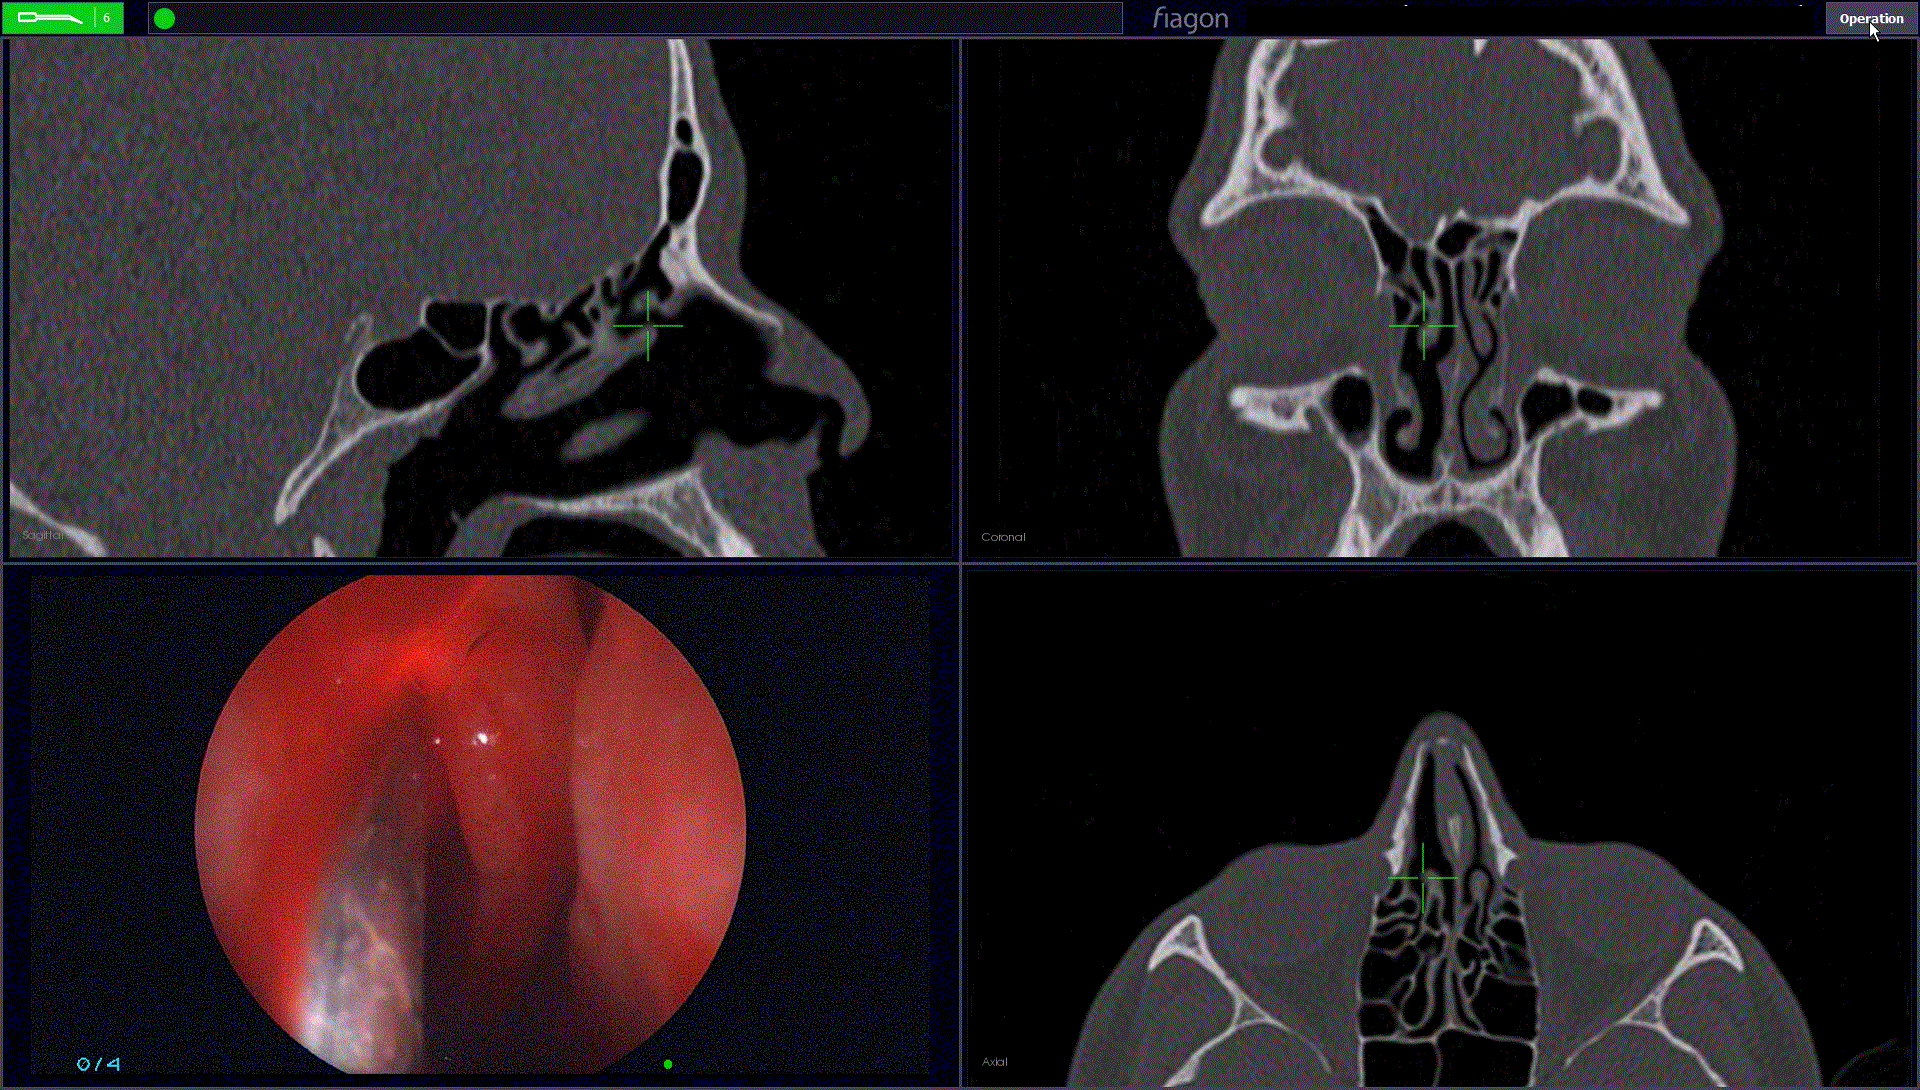

Cet examen d’imagerie est capital pour diagnostiquer la pathologie frontale (sinusite, mucocèle, papillome inversé, tumeur, brèches méningées, méningocèles), et pour planifier l’intervention. Il permet notamment au chirurgien d’utiliser une navigation assistée par ordinateur pour lui permettre de mieux se repérer dans les sinus (sorte de GPS chirurgical) dont la variabilité de l’anatomie est très importante.

Dans le Service ORL du CHU de Caen nous utilisons la neuronavigation magnétique Fiagon qui permet de naviguer à la fois avec un scanner mais aussi si besoin, avec une IRM.